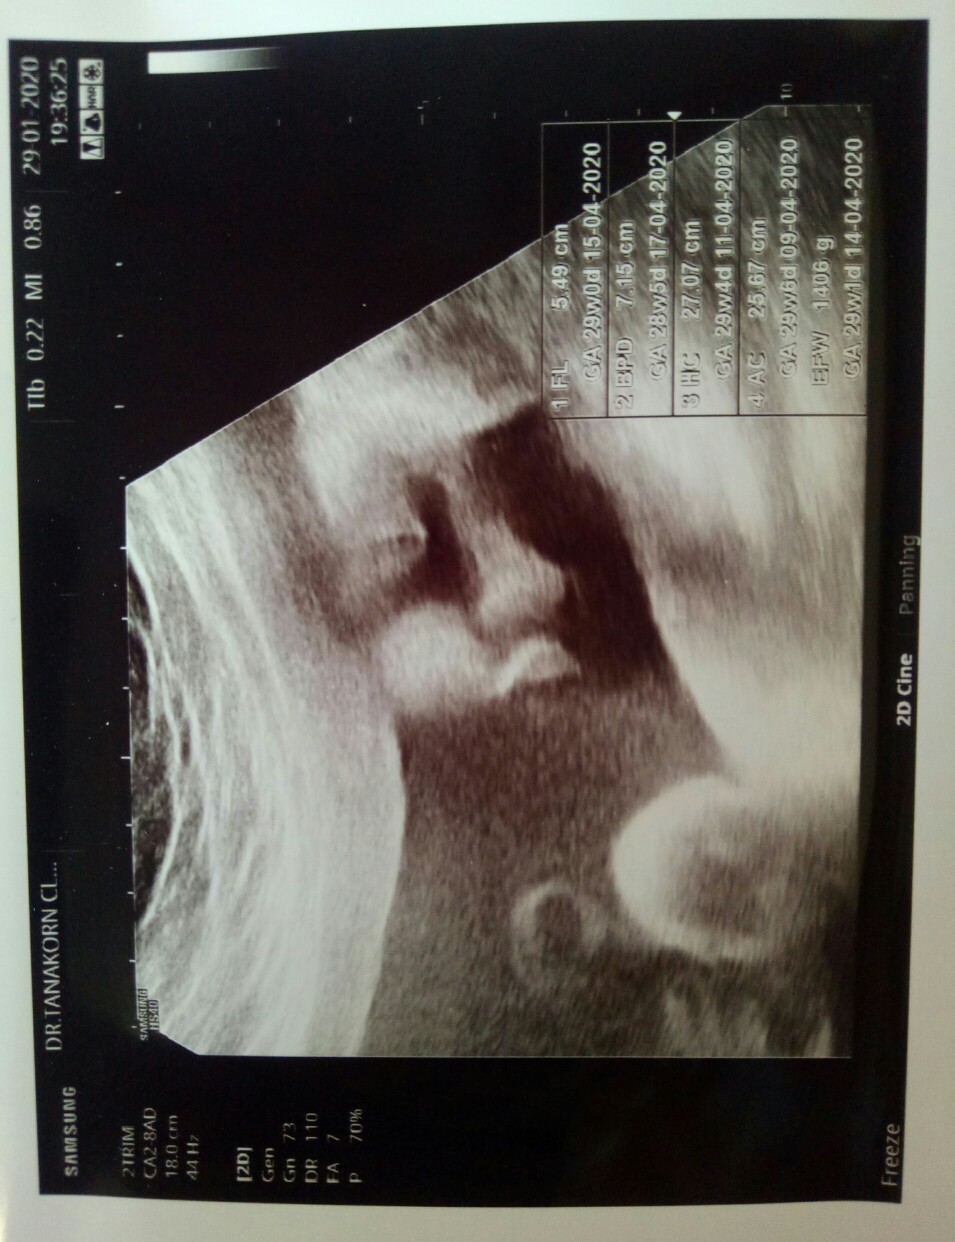

ผู้หญิงค่ะ

ชัดมากก